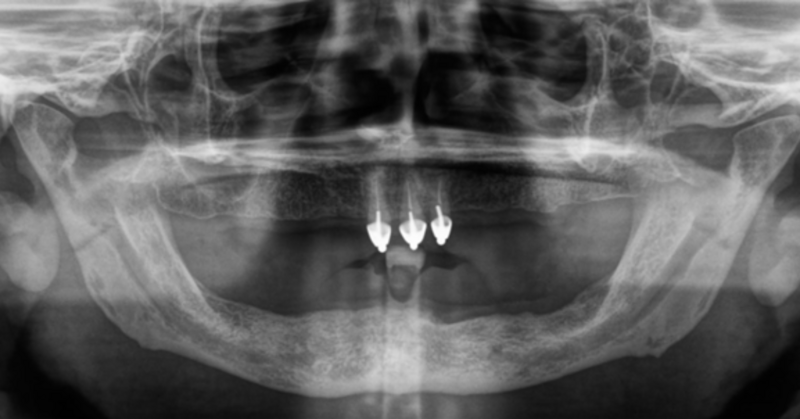

Fast zahnlos über Jahre: Drei Kronen mit Lokatorenspitzen.

Praktische Zahnlosigkeit über Jahre - Erschwerte Therapie durch Makroglossie

Ein Fallbericht von Daniel Liss – Zahnarzt im AllDent Zahnzentrum Leipzig

Der Fall zeigt, dass auch unter widrigen Umständen (lange Zahnlosigkeit, Makroglossie) Full-Arch-Sofortversorgungen auf vier Implantaten möglich sind. Trotz oder möglicherweise gerade wegen der langen Zahnlosigkeit war der Patient bereits mit den provisorischen Brücken sehr gut zurechtgekommen. Durch die Perfektionierung des Bisses konnten Freude und Zufriedenheit über die neuen Zähne noch gesteigert werden. Auch das Behandlungsteam durfte sich schließlich über die erfolgreiche Bissrehabilitation und das Einhalten der guten medizinischen Standards freuen.